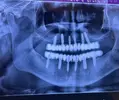

Implant tedavisi